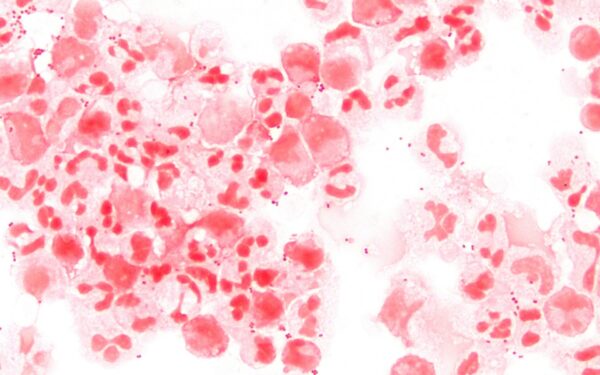

Secretaria de Saúde do município foi notificada sobre o óbito na última quarta-feira (26). Caso segue em apuração. Detalhes da vítima não foram informados. Neisseria meningitidis, a bactéria que causa a meningite meningocócica, foto de arquivo

Wikimedia Uma morte suspeita por meningite é investigada em Juiz de Fora. A informação foi confirmada pela Secretaria Municipal de Saúde ao g1 nesta sexta-feira (28). Compartilhe no WhatsApp Compartilhe no Telegram De acordo com a Prefeitura, a pasta foi notificada na quarta-feira (26) sobre um óbito na cidade. O caso se encontra em investigação. Não foram repassadas informações sobre a vítima. A reportagem entrou em contato com a Secretaria de Estado de Saúde de Minas Gerais (SES-MG) e aguarda retorno. 🔔 O g1 Zona da Mata agora está no WhatsApp. Clique aqui para receber as notícias direto no seu celular! O que é a meningite? As meninges são as membranas que envolvem todo o sistema nervoso central. A meningite ocorre quando há alguma inflamação desse revestimento, causado por micro-organismos, alergias a medicamentos, câncer e outros agentes. O que causa a doença? A doença pode ser causada por bactérias, vírus, fungos e parasitas, segundo o Ministério da Saúde. Segundo a pasta, as meningites virais e bacterianas são as mais importantes para a saúde pública, devido à magnitude da ocorrência e o potencial de produzir surtos. O ministério ressalta ainda que a ocorrência das meningites bacterianas é mais comum no outono-inverno e das virais na primavera-verão. O sexo masculino também é o mais acometido pela doença. Quais são as formas de prevenção? Existem imunizantes no sistema público de saúde que protegem contra a doença. As vacinas disponíveis no calendário de vacinação do Programa Nacional de Imunização são: Vacina meningocócica (Conjugada): protege contra a doença meningocócica causada pelo sorogrupo C. Vacina pneumocócica 10-valente (conjugada): protege contra as doenças invasivas causadas pelo Streptococcus pneumoniae, incluindo meningite. Pentavalente: protege contra as doenças invasivas causadas pelo Haemophilus influenzae sorotipo B, como meningite, e também contra a difteria, tétano, coqueluche e hepatite B. LEIA TAMBÉM: VEJA VÍDEO: Fotógrafa mineira registra erupção de vulcão na Islândia: 'uma das primeiras a presenciar o fenômeno' SEGURANÇA: Familiares de detentos protestam em frente a penitenciárias de Juiz de Fora DECISÃO: Professor universitário demitido trocou mensagens de cunho sexual com aluna da UFV, aponta documento 📲 Confira as últimas notícias do g1 Zona da Mata 📲 Acompanhe o g1 no Facebook e Instagram 📲 Receba notícias do g1 no WhatsApp e no TelegramVÍDEOS: veja tudo sobre a Zona da Mata e Campos das Vertentes